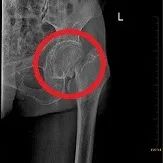

1、股骨頸骨折

術(shù)前

人工股骨頭置換術(shù)后